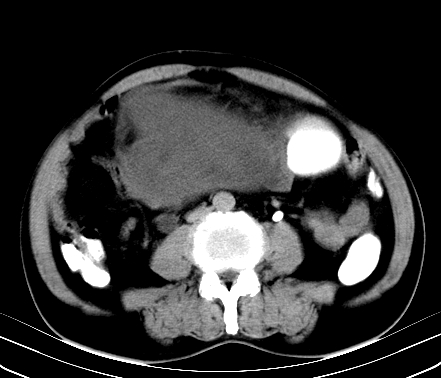

标题: CT19729B:男,74岁,因腿疼就诊,查体触腹部肿物, [打印本页]

标题: CT19729B:男,74岁,因腿疼就诊,查体触腹部肿物,

增强扫描

静脉期

【ct表现】

1、肿块巨大,往往位于腹膜后,长大后才引起症状而就诊;那么位于腹膜后的肿瘤80%为恶性肿瘤。

2、实性肿瘤,增强扫描轻度不均强化,实性肿瘤一般不是好东西。

3、肿瘤边缘似见少许脂肪样密度。

4、腹膜后未见肿大淋巴结,但肿瘤于临近的肠管及组织接触紧密。

【诊断】

腹部占位,考虑位于腹膜后的恶性肿瘤,脂肪肉瘤(实体型)可能性大。

术后病理结果:腹膜后脂肪肉瘤。